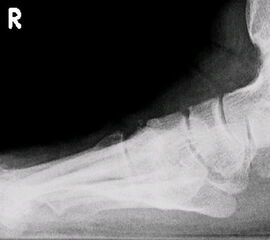

Im seitlichen Röntgenbild werden dorsale Osteophyten des Großzehengrundgelenkes als Ausdruck arthrotischer Veränderungen des Grundgelenkes befundet, eine nach dorsal gewinkelte Stellung der Oberkante des Metatarsale I im Verhältnis zum Metatarsale II deutet auf eine Elevatusposition des 1. Strahles hin (Abb. 7). Gelegentlich kann im seitlichen Röntgenbild ein plantares Klaffen des TMT I als Ausdruck einer Instabilität zu sehen sein (Abb. 8). Parallel verlaufende Metatarsalia I und II sind jedoch keinesfalls ein sicherer Beweis für das Fehlen einer Insuffizienz des 1. Strahles, da die Stellung der beiden Metatarsalia zueinander durch Rückfuß-Valgusdeformitäten fehlprojiziert sein kann.